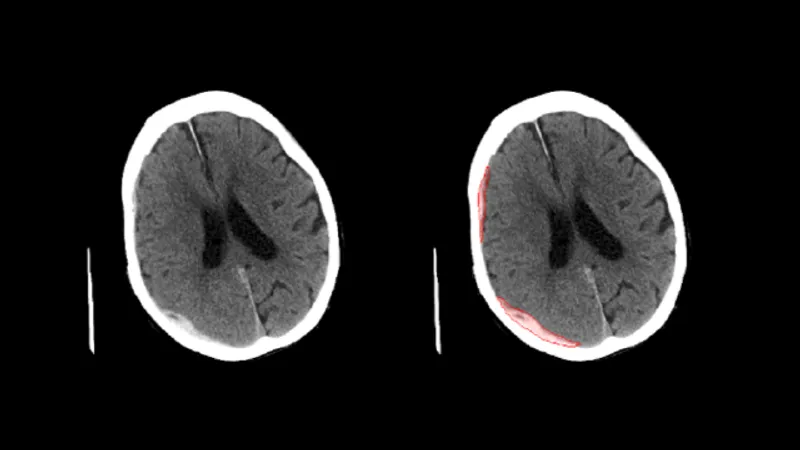

頭部CT画像から 高吸収/低吸収領域及び組織構造・境界の不明瞭化がみられる領域の抽出

頭部単純 CT 画像情報から高吸収・低吸収領域、組織構造・境界の不明瞭化領域の抽出を行います。

頭部単純 CT 画像の画像情報から、画像に基づく画素値の分析を行い、以下の情報を提供します。 (1) 頭蓋内で周囲及び前後のスライスと比べ高吸収の領域 (2) 頭蓋内で周囲及び前後のスライスと比べ低吸収の領域 (3) 頭蓋内で前後のスライス及び同一スライス内の左右で比較して組織構造もしくは組織境界